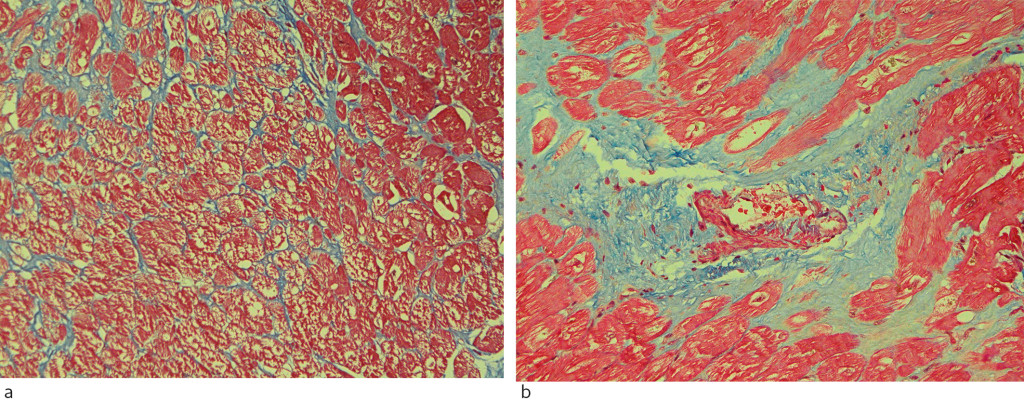

Biological specimen

Biomarkers for fibrosis can be measured in myocardial biopsies and blood tests. Myocardial biopsies are taken from explanted hearts or during myectomy, open heart surgery or catheter-based endocardial biopsy. With heart biopsies and using appropriate staining methods, histological analysis of the volume fraction of collagen is regarded as the gold standard for detection of fibrosis (7, 10, 17). Total collagen can be quantified, and the type (intrastitial or replacement) and extent of fibrosis can be described (Figure 4). Limitations are associated with possible non-representative biopsy, purely local assessment, limited amount of tissue and procedure-related risk (15), (17–19). Modern molecular biology methods can also be used, but should be validated against histology prior to clinical use (18).

Hypertrophic cardiomyopathy is a genetic disease that can cause extensive myocardial fibrosis (37) (Figure 4). Fibrosis and function impairment are often greatest in the basal septum (38). High late contrast enhancement in MRI is associated with increased risk of sudden cardiac death (39). Interstitial fibrosis is more strongly associated with arrhythmias than replacement fibrosis (37).